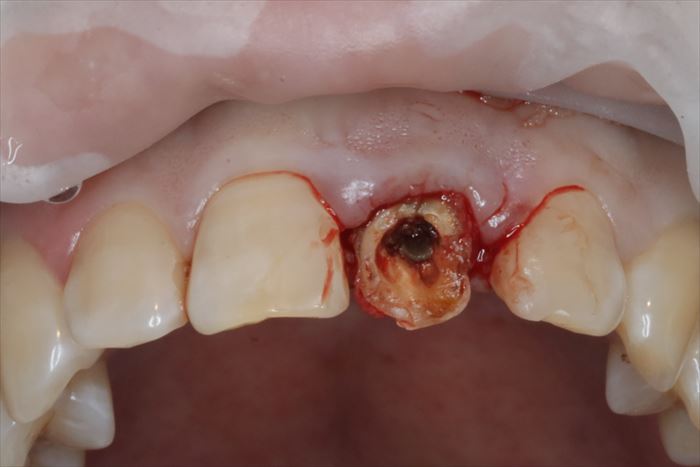

では、いよいよ仮歯を外して抜歯即時インプラント埋入オペのスタートです。

歯肉が歯根の上面をカバーするように増殖して覆い隠しています。

増殖して覆い隠している歯肉は正常像ではありませんので必要最小限切除して抜歯します。